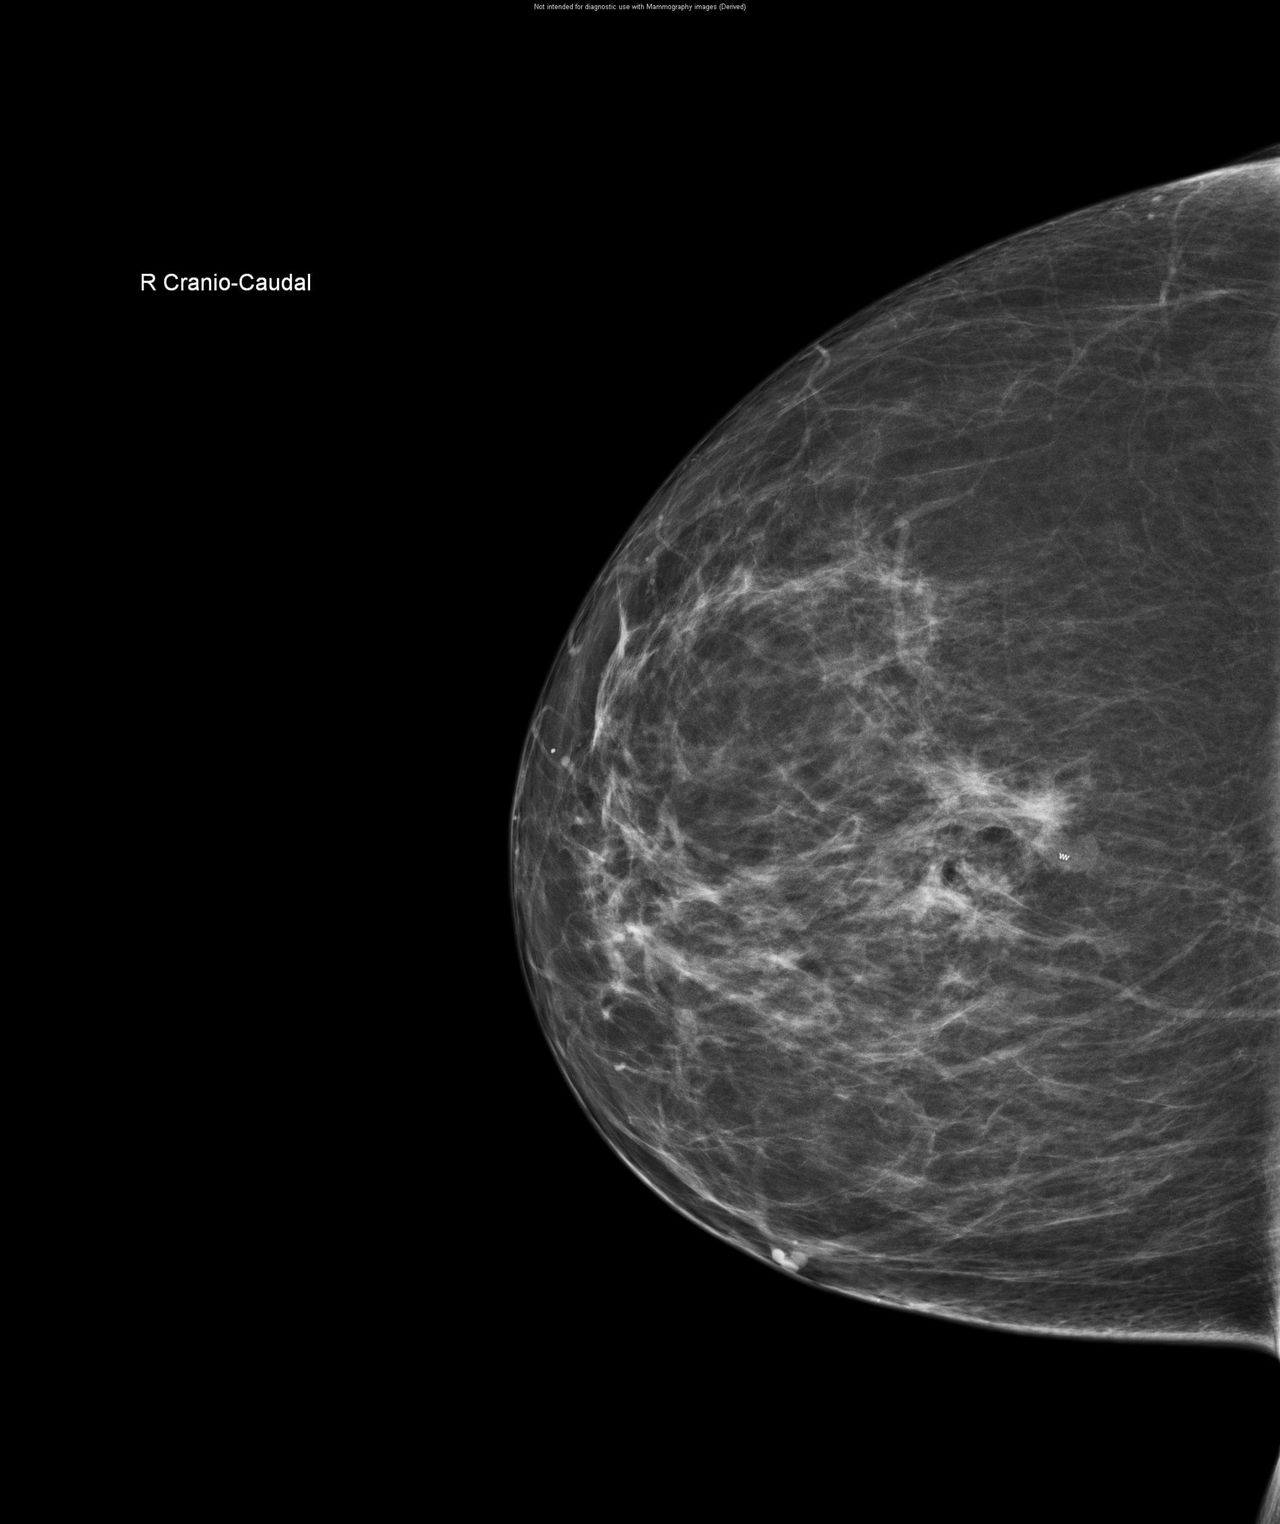

CESM is an advanced form of mammography that uses a safe dye injected into the bloodstream. This dye highlights areas of concern within the breast, giving clinicians a much clearer and more detailed image than a traditional mammogram.

“Sometimes it can be difficult to interpret a mammogram, especially in patients with dense breast tissue”, Nicole explains. “It’s a bit like looking for a cloud in a sky full of clouds. The contrast helps remove that ‘noise’ and shows us exactly what’s going on inside the breast.”

One of the biggest advantages of CESM is that it can be carried out during the patient’s breast clinic appointment and reviewed by a radiologist straight away. Before CESM was introduced, patients with unclear mammogram results often faced a longer wait for further tests, such as an MRI scan, to gather more information.

“A patient came to us with a lump in one breast. When we used CESM, we also spotted abnormality in the other breast. This enabled both breasts to be dealt with at the same time which would not have been possible otherwise.”